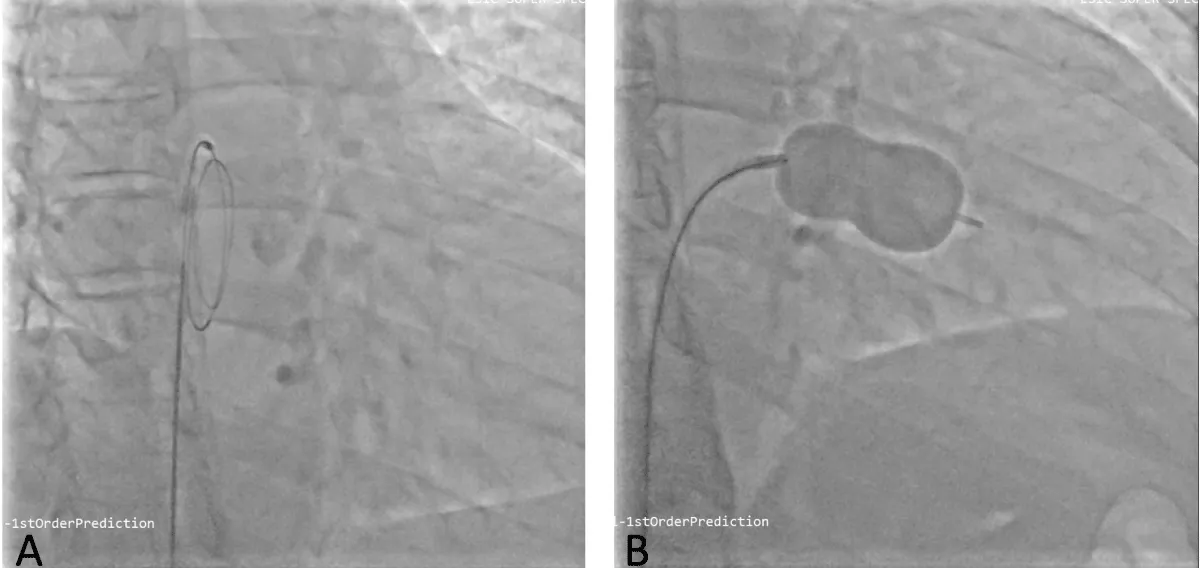

After obtaining consent, access was obtained through the right femoral vein and artery. Under 4D Transesophageal Echocardiography (4D TEE) guidance, the first transseptal puncture was performed with a broken Brough needle, and the LA wire was inserted through femoral venous access (Figure 1). Right femoral artery access was used for retrograde crossing of the aortic valve (AV) (Figure 2), and a Teflon wire was placed in the left ventricle. The aortic valve (AV) was dilated with a 14 mm ATLAS GOLD (BARD) balloon (Figure 3, Video 1).

Download Image

Figure 1: A,B: 4Dimensional multiplanar transoesophageal echocardiography. A. 4D image with Left atrial wire, B. Severe mitral stenosis with mitral area of 0.5 cm2, 1C &1D. Showing multiplane of mitral valve.